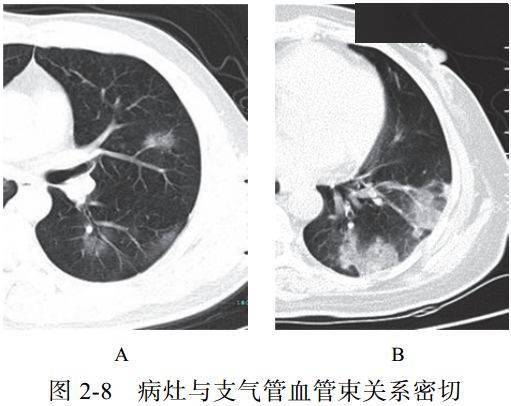

(八)病灶沿支气管血管束分布

较多病灶常沿着支气管血管束分布,从外周向中央进展亦如此表现

提示病理改变:病毒肺炎病灶常沿着间质分布蔓延(图 2-8)